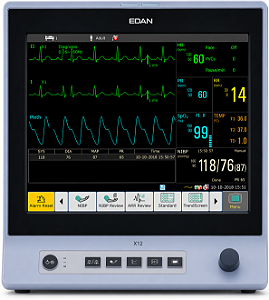

Monitor Multiparamétrico X12 (SPO2-ECG-PNI-TEMP-RESP) TELA 12'' - EdanR$ 7.400,00até 6x de R$ 1.233,33 sem jurosou R$ 7.030,00 via Pix

Monitor Multiparamétrico X12 (SPO2-ECG-PNI-TEMP-RESP) TELA 12'' - EdanR$ 7.400,00até 6x de R$ 1.233,33 sem jurosou R$ 7.030,00 via Pix -